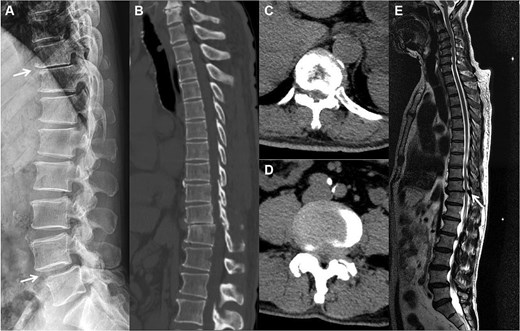

A 66-year-old male presented with a 1-year history of progressive low back pain and bilateral lower limb numbness, intensifying over the preceding month. Symptoms began insidiously without trauma and progressively worsened with prolonged standing and walking, improving with rest. The patient described deep, aching pain that significantly impacted his daily activities. Physical examination revealed bilateral lower limb numbness, especially prominent in the anterior thighs, an unsteady gait with a broad-based stance, decreased quadriceps muscle strength, reduced sensation below the navel extending to the groin, and positive bilateral Babinski signs indicating upper motor neuron involvement. Initial external X-rays suggested only L4 vertebral displacement, inconsistent with the clinical findings, prompting hospital admission for further evaluation. Refined imaging studies revealed previously unrecognized pathology. X-ray (Fig. 1A) and CT (Fig. 1B–D) demonstrated concomitant T10 vertebral body slippage, while MRI (Fig. 1E) showed severe T10/11 spinal cord compression with associated signal changes. The patient was diagnosed with thoracic spinal stenosis due to T10–T11 vertebral slip, explaining the bilateral lower extremity neurological symptoms and gait instability. Given the prolonged symptom duration, recurrent nature, and functional impact, surgical intervention was indicated after multidisciplinary discussion. The patient underwent T10–T11 thoracic interbody fusion with comprehensive decompression under general anesthesia. The procedure included herniated disc material removal, extensive posterior decompression, precise pedicle screw and titanium rod placement for stabilization, and autologous iliac crest bone grafting for interbody fusion. Postoperative management included comprehensive pain control and neurological monitoring. Follow-up X-ray (Fig. 2A and B) and CT (Fig. 2C–E) demonstrated successful vertebral realignment with the internal fixation in the ideal position. By postoperative Day 6, the patient reported significant back pain and leg numbness relief. Progressive improvement with structured physical therapy led to discharge on Day 10. One-year follow-up examination (Fig. 3) revealed stable fixation with continued symptom resolution, enabling free ambulation and complete return to normal activities.

The preoperation imaging examinations. A sagittal X-ray (A) shows concomitant anterior displacement and instability of T10 and L4. A sagittal CT image (B) similarly demonstrates vertebral body slippage at T10, with stenosis and disc herniation of the spinal canal at the corresponding segments (C, D). T2-weighted imaging MRI (E) demonstrates severe spinal cord compression, with neurologic ischemic degeneration.